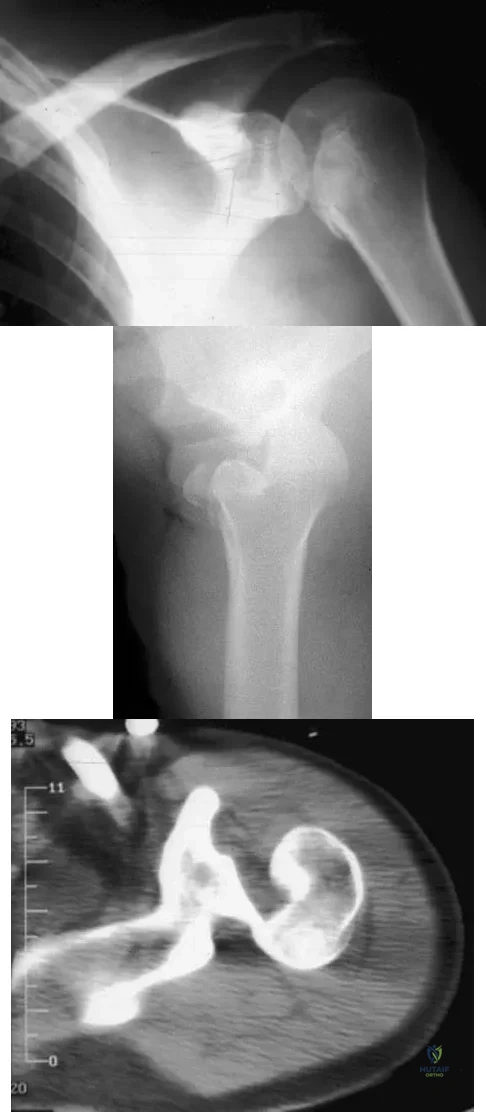

A 21-year-old patient has had pain and a marked decrease in active and passive shoulder motion after having had a seizure 2 months ago as the result of alcohol abuse. Current AP and axillary radiographs and a CT scan are shown in Figures 26a through 26c. Management should consist of

Detailed Explanation